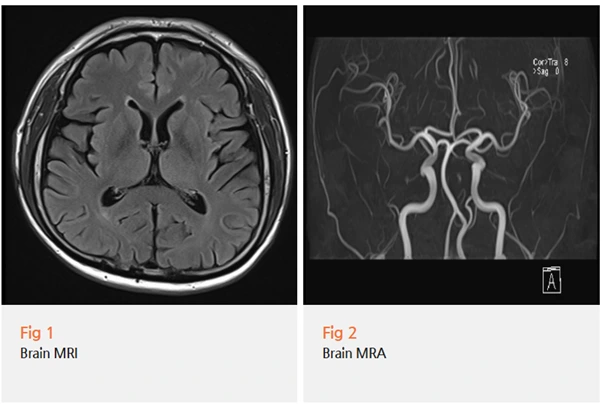

귀 주변 통증과 두통이 함께 있을 때는...

일단 뇌에 문제가 없는지부터 확인해야 해요.

뇌신경 이상이나 혈관 문제일 가능성을 배제해야 하거든요.

환자분께 당일 뇌 MRI, MRA 검사를 권해드렸습니다.

하지만 이건 정말 필수 과정이에요.

안전하게 진단하려면 중추신경계 병변을 먼저 확인해야 하니까요.

다행히 검사 결과는...

뇌에는 아무런 문제가 없었습니다.